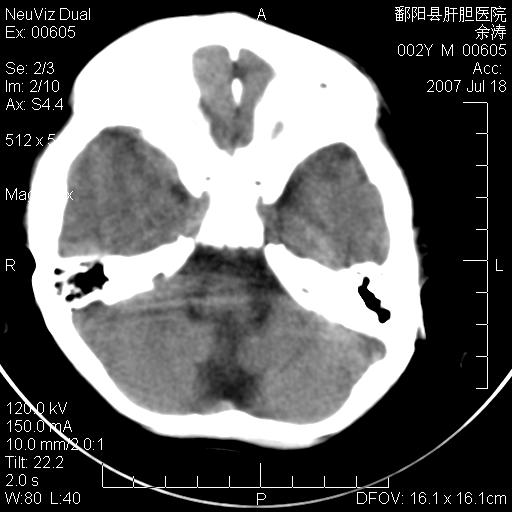

男性 2岁:平时智力障碍。外伤后行颅脑平扫。

左颞叶“萎缩”,可见不规则高密度影,并左侧室扩大,呈负占位效应...支持考虑先天发育异常(血管发育畸形)可能性大,建议结合进一步检查了解。

左颞叶“萎缩”其内可见不规则点条状高密度影,并左侧室扩大,考虑颅面血管瘤病

脑裂畸形;左侧脑脑萎缩;透明隔囊肿;血管畸形?

开唇型脑裂畸形

左侧颞顶叶钙化灶,其内有小片状低密度影 边缘清晰。与之相邻的脑沟增宽增深 ,左侧侧脑室体部牵拉扩大。考虑左颞顶软化灶并局限性脑萎缩。透明隔间腔。

该病人应该还有胼胝体发育不全